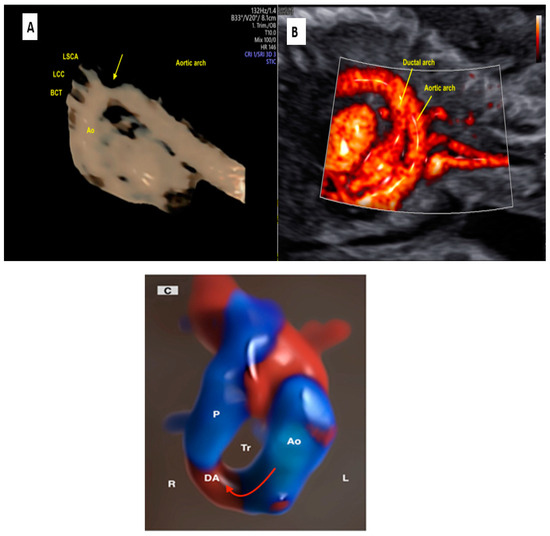

2.4. Aortic and Ductal Arch Anomalies

- Hirano, Y.; Masuyama, H.; Hayata, K.; Eto, E.; Nobumoto, E.; Hiramatsu, Y. Prenatal Diagnosis of Interrupted Aortic Arch: Usefulness of Three-Vessel and Four-Chamber Views. Acta Med. Okayama 2016, 70, 485–491. [Google Scholar] [PubMed]

- Zhang, S.; Wang, N.; Qu, P.; Shu, X.; Mi, Y.; Gao, X. Prenatal echocardiography diagnosis of a novel combination of bilateral ductus arteriosus and cardiovascular anomalies: A case report and literature review. Front. Cardiovasc. Med. 2024, 11, 1389759. [Google Scholar] [CrossRef]